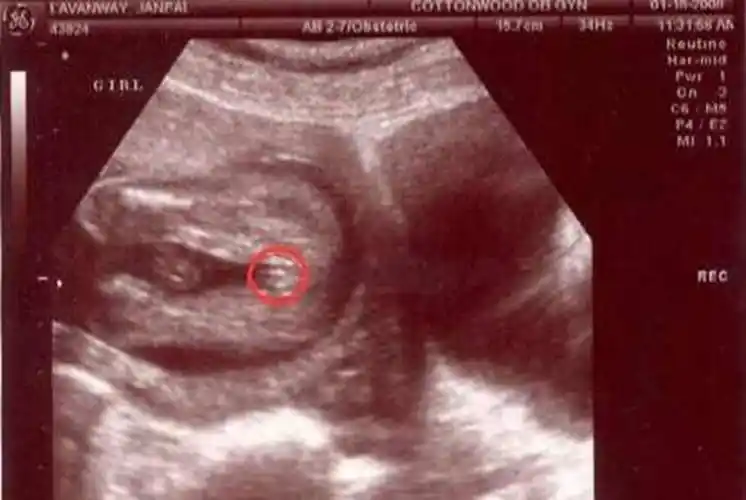

b超大排畸能看胎儿性别吗?